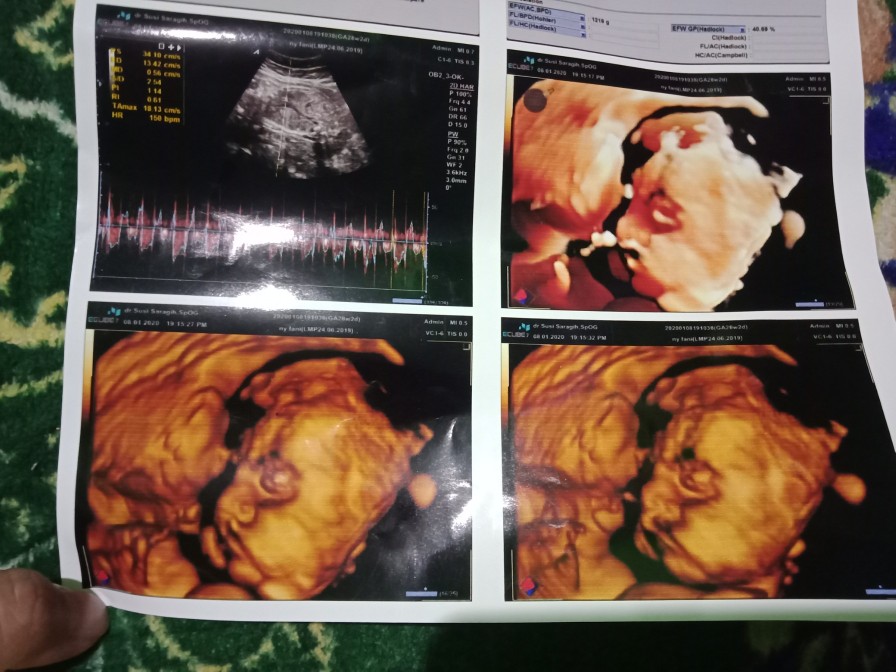

28 week